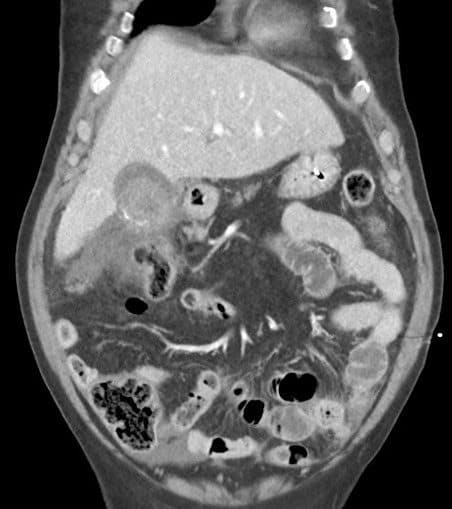

Vỡ túi mật

» Thông tin: Nam giới – 80 tuổi.

» Lâm sàng: Chấn thương.